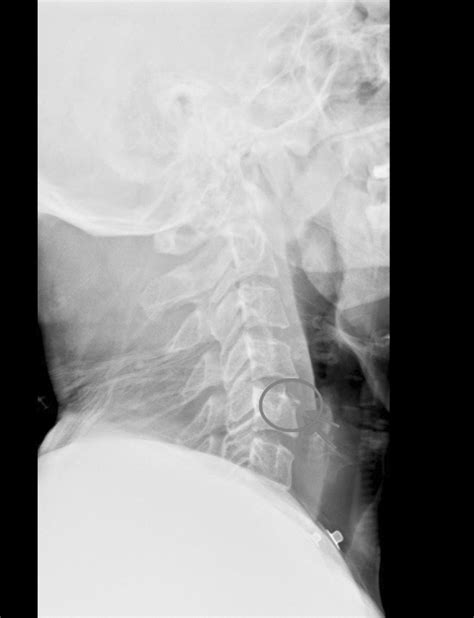

X-ray of a spine

When reviewing Cervical Vertebrae Pics, you may occasionally see signs of pathology, such as bone spurs or disc degeneration. Because the neck is subjected to significant stress from modern habits—such as “text neck” caused by prolonged screen time—these vertebrae are susceptible to wear and tear. Seeing an image of a healthy spine compared to one experiencing spondylosis or herniated discs provides a stark reminder of the importance of posture and spinal health.